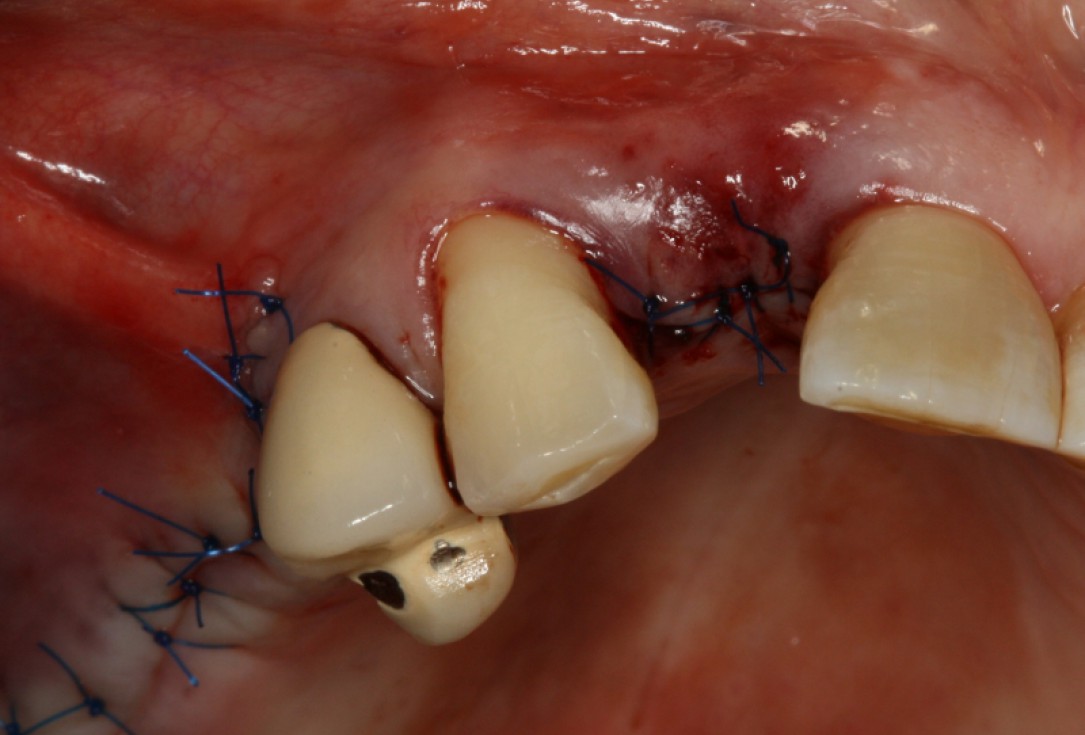

10/20 - wound closureGBR with maxresorb® & Jason® membrane - Prof. Dr. Dr. D. Rothamel

19/20 - SuturingGBR with maxresorb® & Jason® membrane - Prof. Dr. Dr. D. Rothamel